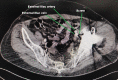

Case report: We present this challenging and unique case of a 64-year-old female patient where the acetabular component screw was found to be adherent to the external iliac vessels, with vascular injury imminent. During revision surgery, the iliac vessels were first released free of all adhesions with the intrapelvis screw using an ilioinguinal incision and retroperitoneal approach. The prosthesis was removed using a posterior approach to the hip joint. Definitive surgery was performed after 2 weeks.

Conclusion: Surgeons should be cognizant of the possibility of an avulsion vascular injury in revision cases having intrapelvic screws or implants. The proximity of such an implant with the intrapelvic vasculature must be confirmed preoperatively. Management should be individualized. Dual approach and staged procedure help in a favorable outcome. Vascular injury, revision total hip arthroplasty, screw abutting iliac vessel, external iliac vessel, computed tomographic angiography.